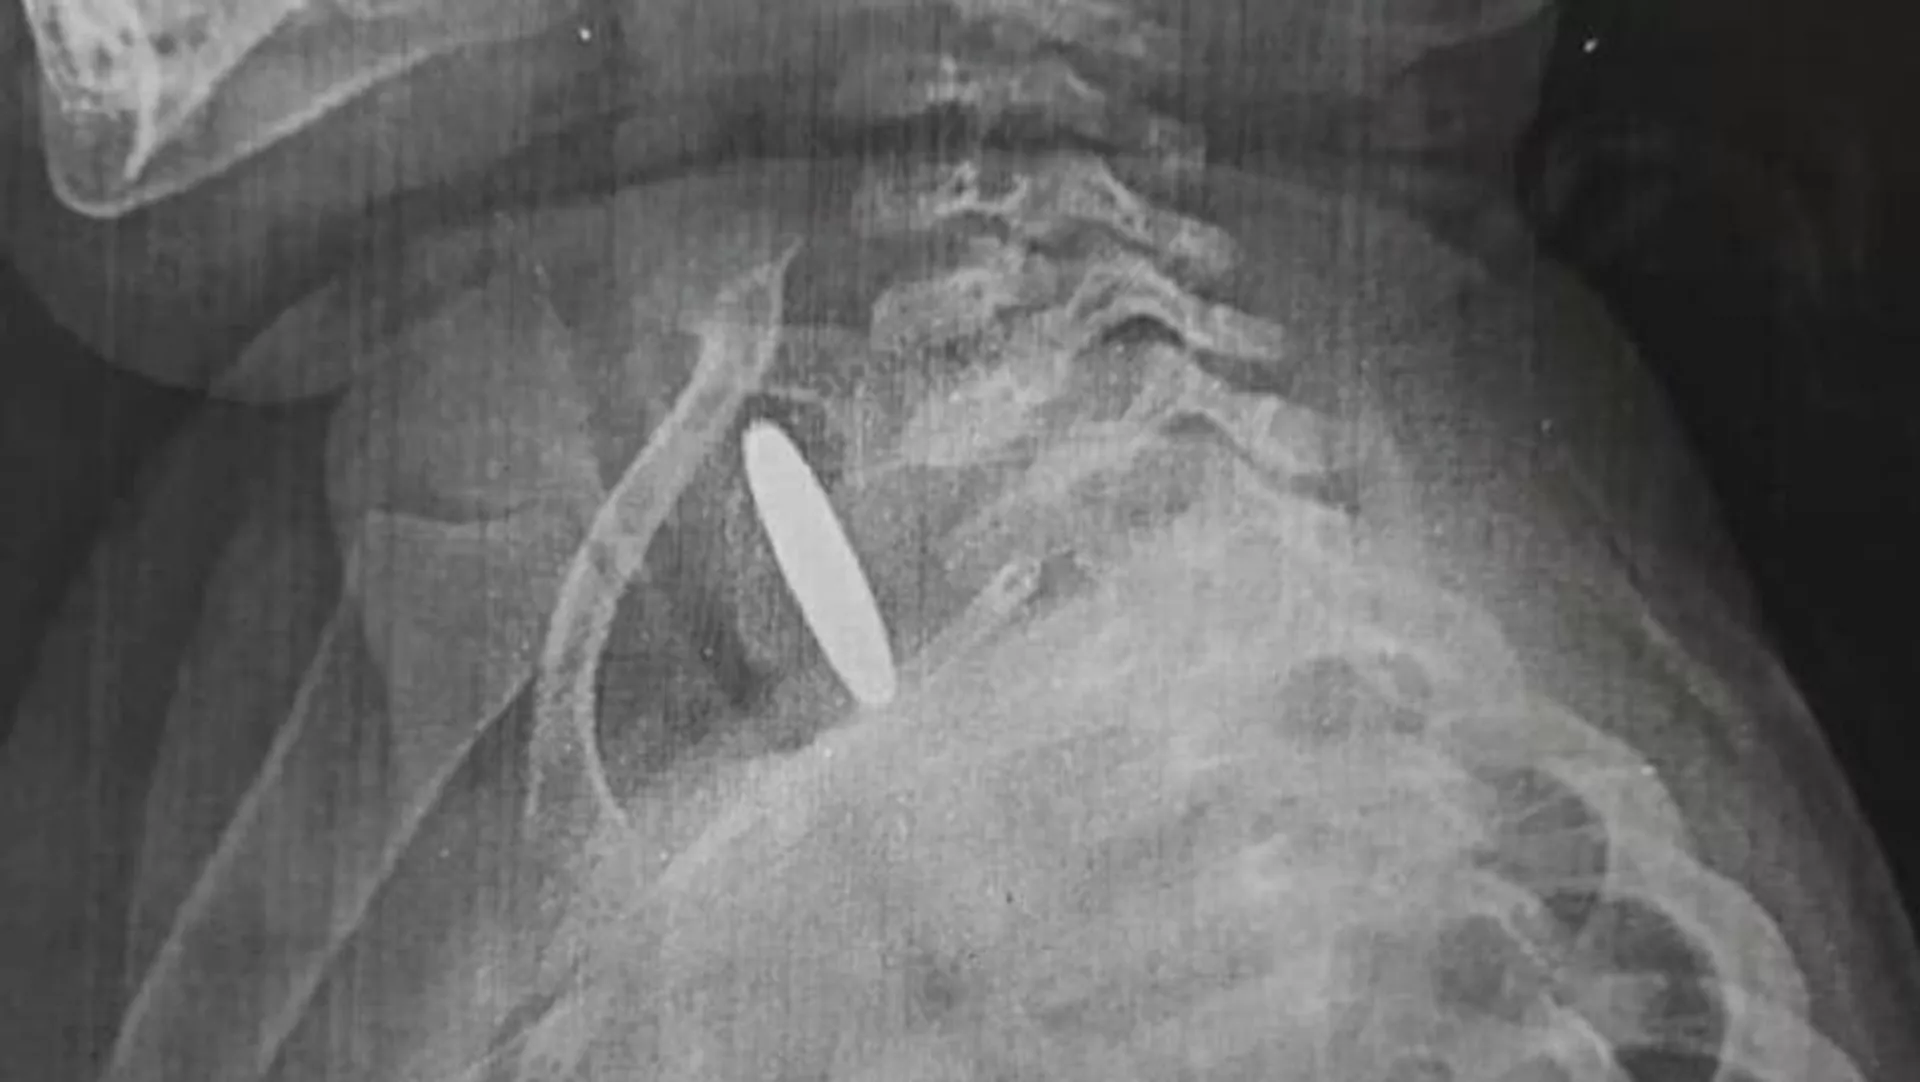

БИШКЕК, 11 сен — Sputnik. В Оше двухлетняя девочка проглотила монету. Посторонний предмет два месяца был в ее пищеводе. Об этом сообщает Ошская межобластная детская клиническая больница.

Предположительно, это монета номиналом 5 сомов.

По словам врачей, родители и родственники все это время не замечали неладного. Ребенок иногда кашлял, в остальном все было нормально. Девочку прооперировали в межобластной больнице. Сейчас состояние ребенка хорошее. Врачи призывают родителей следить за детьми.